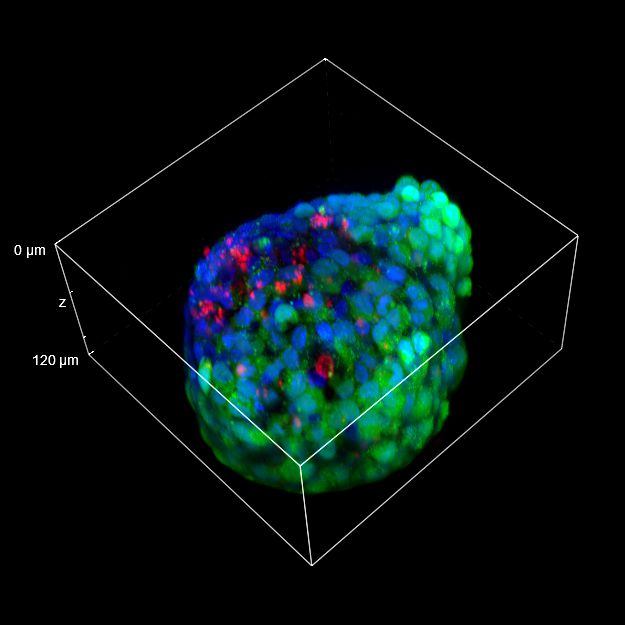

为了更好地理解 3D 细胞组织,在图 C 中,我们展示了使用两种物镜获得的同一球体的体积视图(120 um 厚),甚至在 3D 肿瘤球体的更深区域也能看到染色。最后,在 图 D 中,显示了使用 25 倍硅油物镜获得的整个球体的 3D 电影特效。

使用 20 倍空气物镜和使用 25 倍硅油物镜获得的图像之间的比较(图 A、B 和 C)突出了基于生物应用的透镜选择的重要性。从 20 倍到 25 倍的转换导致分辨率提高(基于 25 倍的 NA 大于 20 倍 NA),这当然会影响图像质量,并且还会导致光折射减少。事实上,浸油通过用更高折射率的介质代替透镜和盖玻片之间的空气间隙,大大提高了显微镜的分辨率,从而减少了光的折射。

在 3D 成像中,样品的折射率与其浸没介质的折射率相匹配对于深层组织观察至关重要。硅酮浸油非常适合透过厚厚的生物样本进行成像;它与细胞和封固剂的折射率非常吻合,与使用普通 20 倍空气物镜获得的图像相比,减少了球面像差,产生了更亮、分辨率更高的图像。

图 C:使用 20 倍空气物镜(左)和 25 倍硅油物镜(右)获得的球体的 3D 体积视图。活细胞用钙黄绿素(绿色)标记,死细胞用 PI(红色)标记。细胞核用 Hoechst(蓝色)染色。沿 Z 轴的比例尺:120 um。这些图像是使用 CrestOptics X-Light V3 转盘获取的。